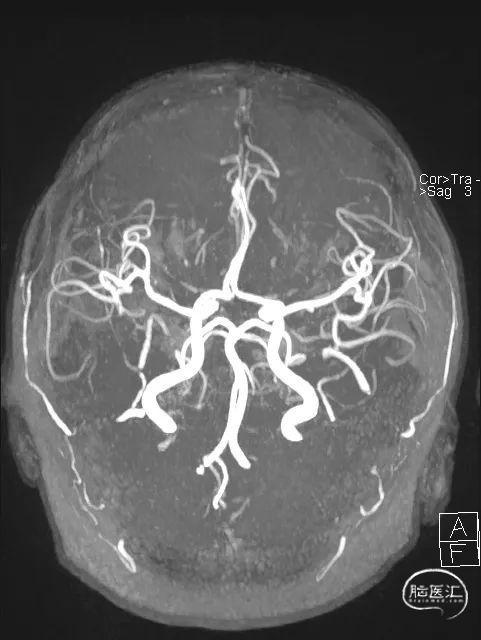

术前造影:左侧优势椎动脉,基底动脉闭塞。

左侧颈内动脉造影可见动脉末期软膜支略有向后枕部代偿。